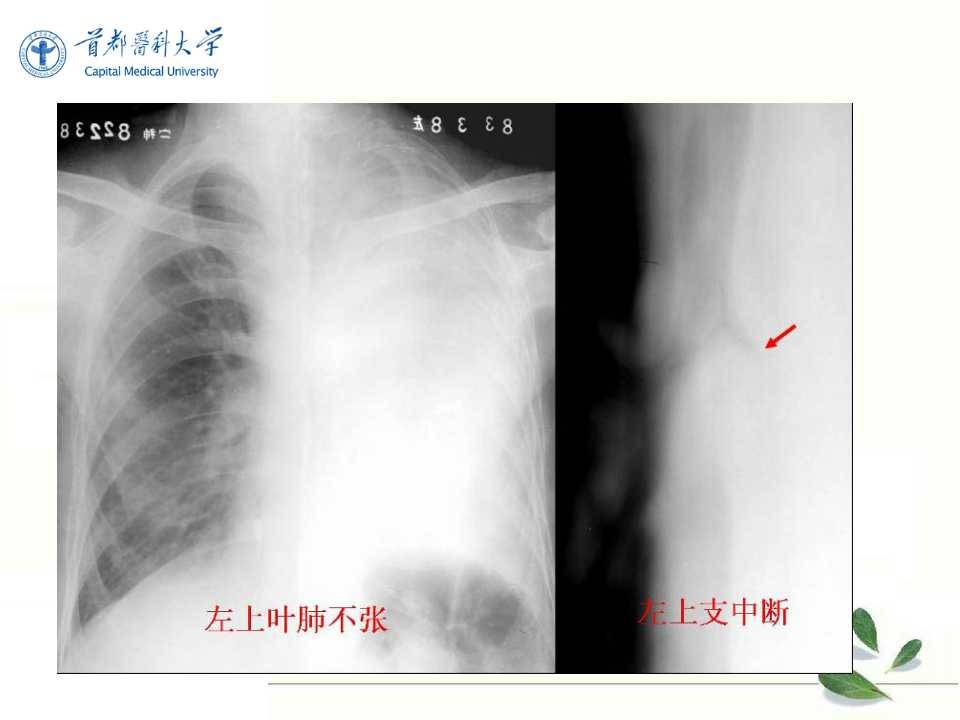

肺癌的影像学检查